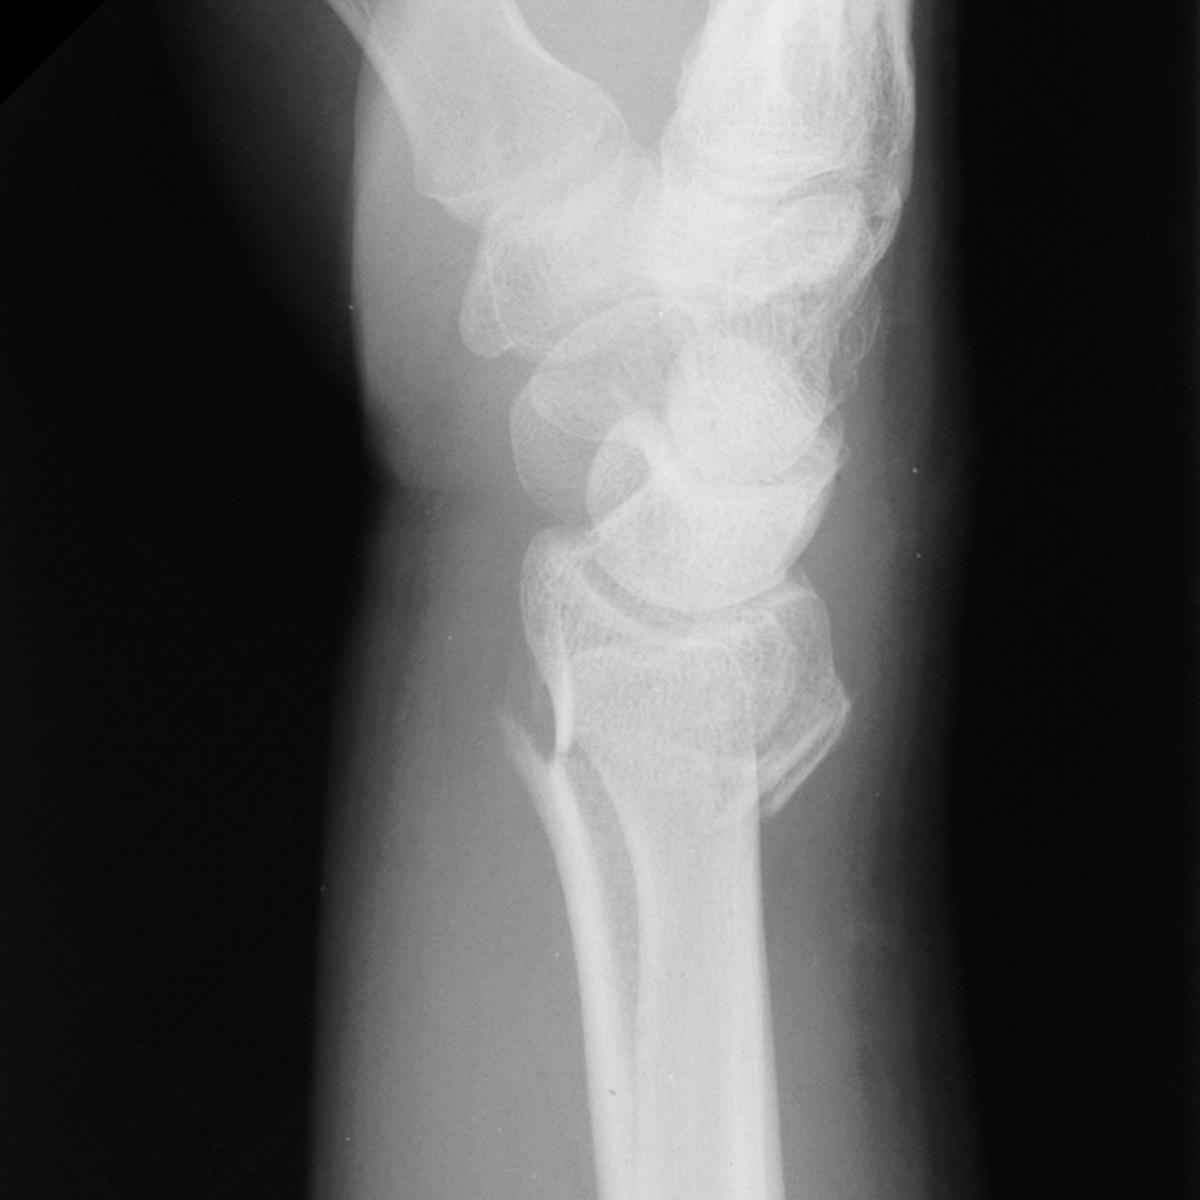

| Case 6 Extraarticular distal radius fracture with angulation and dorsal comminution. |

| Attempts at

closed reduction alone were unsuccessful. |

| Freer elevator

introduced percutaneously as a reduction aid. |

| Percutaneous

fracture stabilization with three pins via the

dorsal radial tubercle, radial styloid and FCR

portals. |

| Pins were left

protruding and bent to overlap. |

| Thermoplastic-pin

construct at 6 weeks, immediately prior to removal. |

| Late result. |